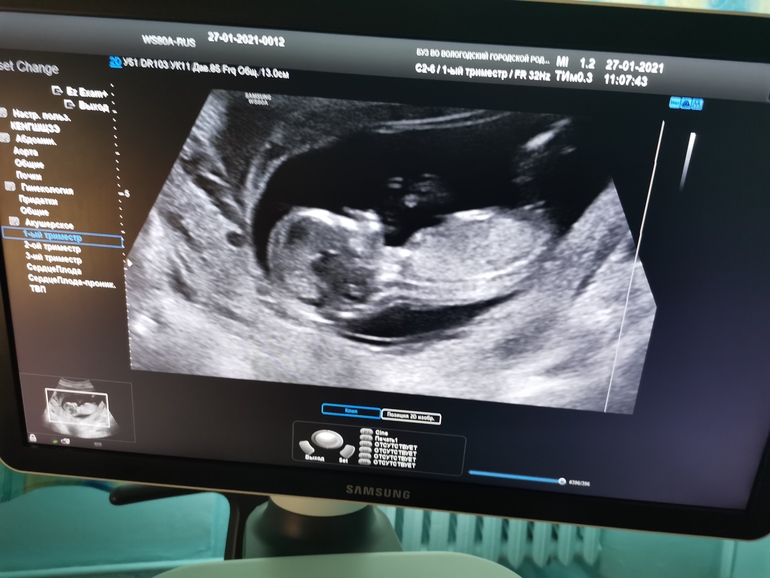

Посмотрите, кто в домике?

Результаты: УЗИ, КТГ, доплера, скринингаДевочки, со всеми этими переживания изза первого скрининга и мазни, забыла выложить фото отростка))

Как кто думает, кто в домике?!

Чтобы предполагать пол, нужно видеть половой бугорок, которого здесь на фото нет))

Половой бугорок есть и у мальчиков, и у девочек. Там пол зависит от градуса полового бугорка. И на фото его нет, потому что просто не видно, ребенок лежит полубоком + то место, где половой бугорок, не засвечено.

Не совсем понятно... По-моему, здесь малышок развернут почти спинкой, а нужно чётко профиль))

Так-то, я девочку увидела, но это не точно.